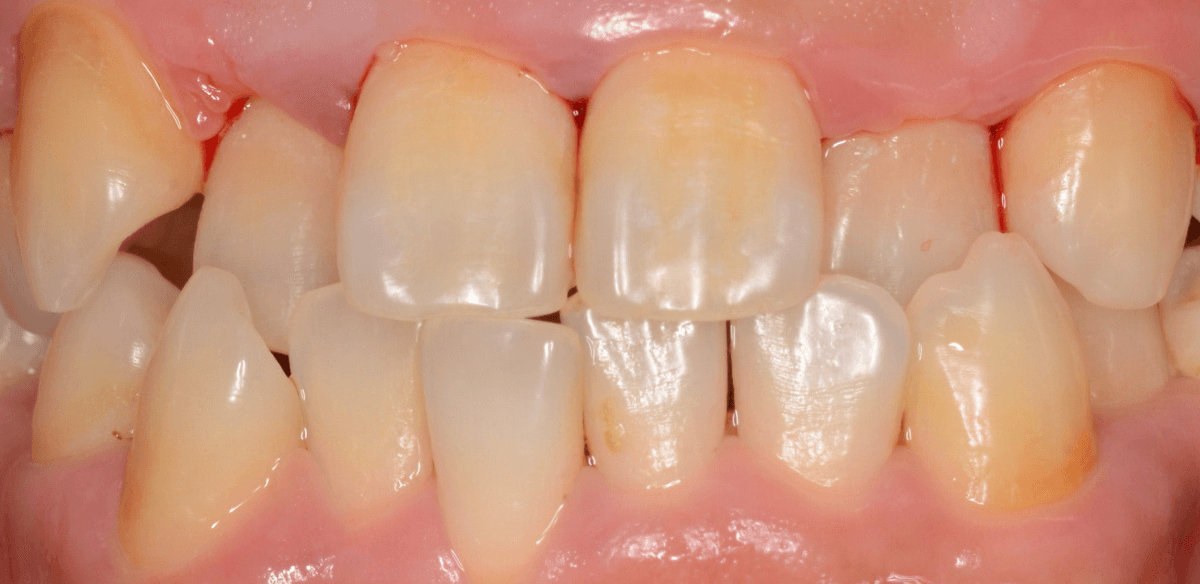

Case.2

今回は、上の前歯の縁下歯石の除去をしたお話です。

写真の左の矢印の歯肉が退縮して腫れています。

右の矢印の歯肉と比べてみるとわかると思います。

こういった歯肉の形をしている部分は、歯石がたまっていることが多いです。

拡大してみると、縁下歯石(歯肉の中に入り込んだ歯石:歯肉に大きく悪影響を与えます)が顔を出しているのがわかります。

かなり歯肉の中に歯石が入り込んでしまっていると思われます。

歯肉の中の歯石は歯にべっとりとこびりつきますので、除去するには麻酔をして引きはがす処置が必要です。

歯石除去後、約1週間です。

歯肉がひきしまってきたのがわかるでしょうか。

治療前との比較です。

比べると、違いがわかると思います。

まだ若い患者さんで本格的な歯周病に進行する前ですので、歯ブラシの徹底によって、もっと歯肉が改善されるのも期待できます。

その後、この患者さんは熱心に通院とお手入れをされて、約二か月が経ちました。

歯肉は順調に引き締まってきました。

歯周治療は、ご本人のメンテナンスなしには結果が出ません、頑張ってらっしゃる形が見えて、とても嬉しいですね

こちらが比較写真です。

並べてみると、治り具合がよりわかりますね